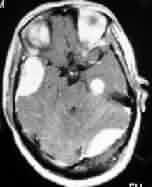

|

|

|

Meningioma with

Associated pituitary adenoma-MRI

|

Olfactory groove

meningioma-MRI

|